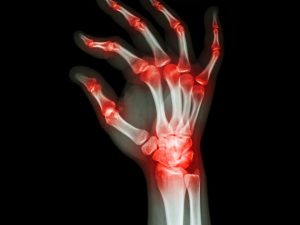

rheumatoid arthritis